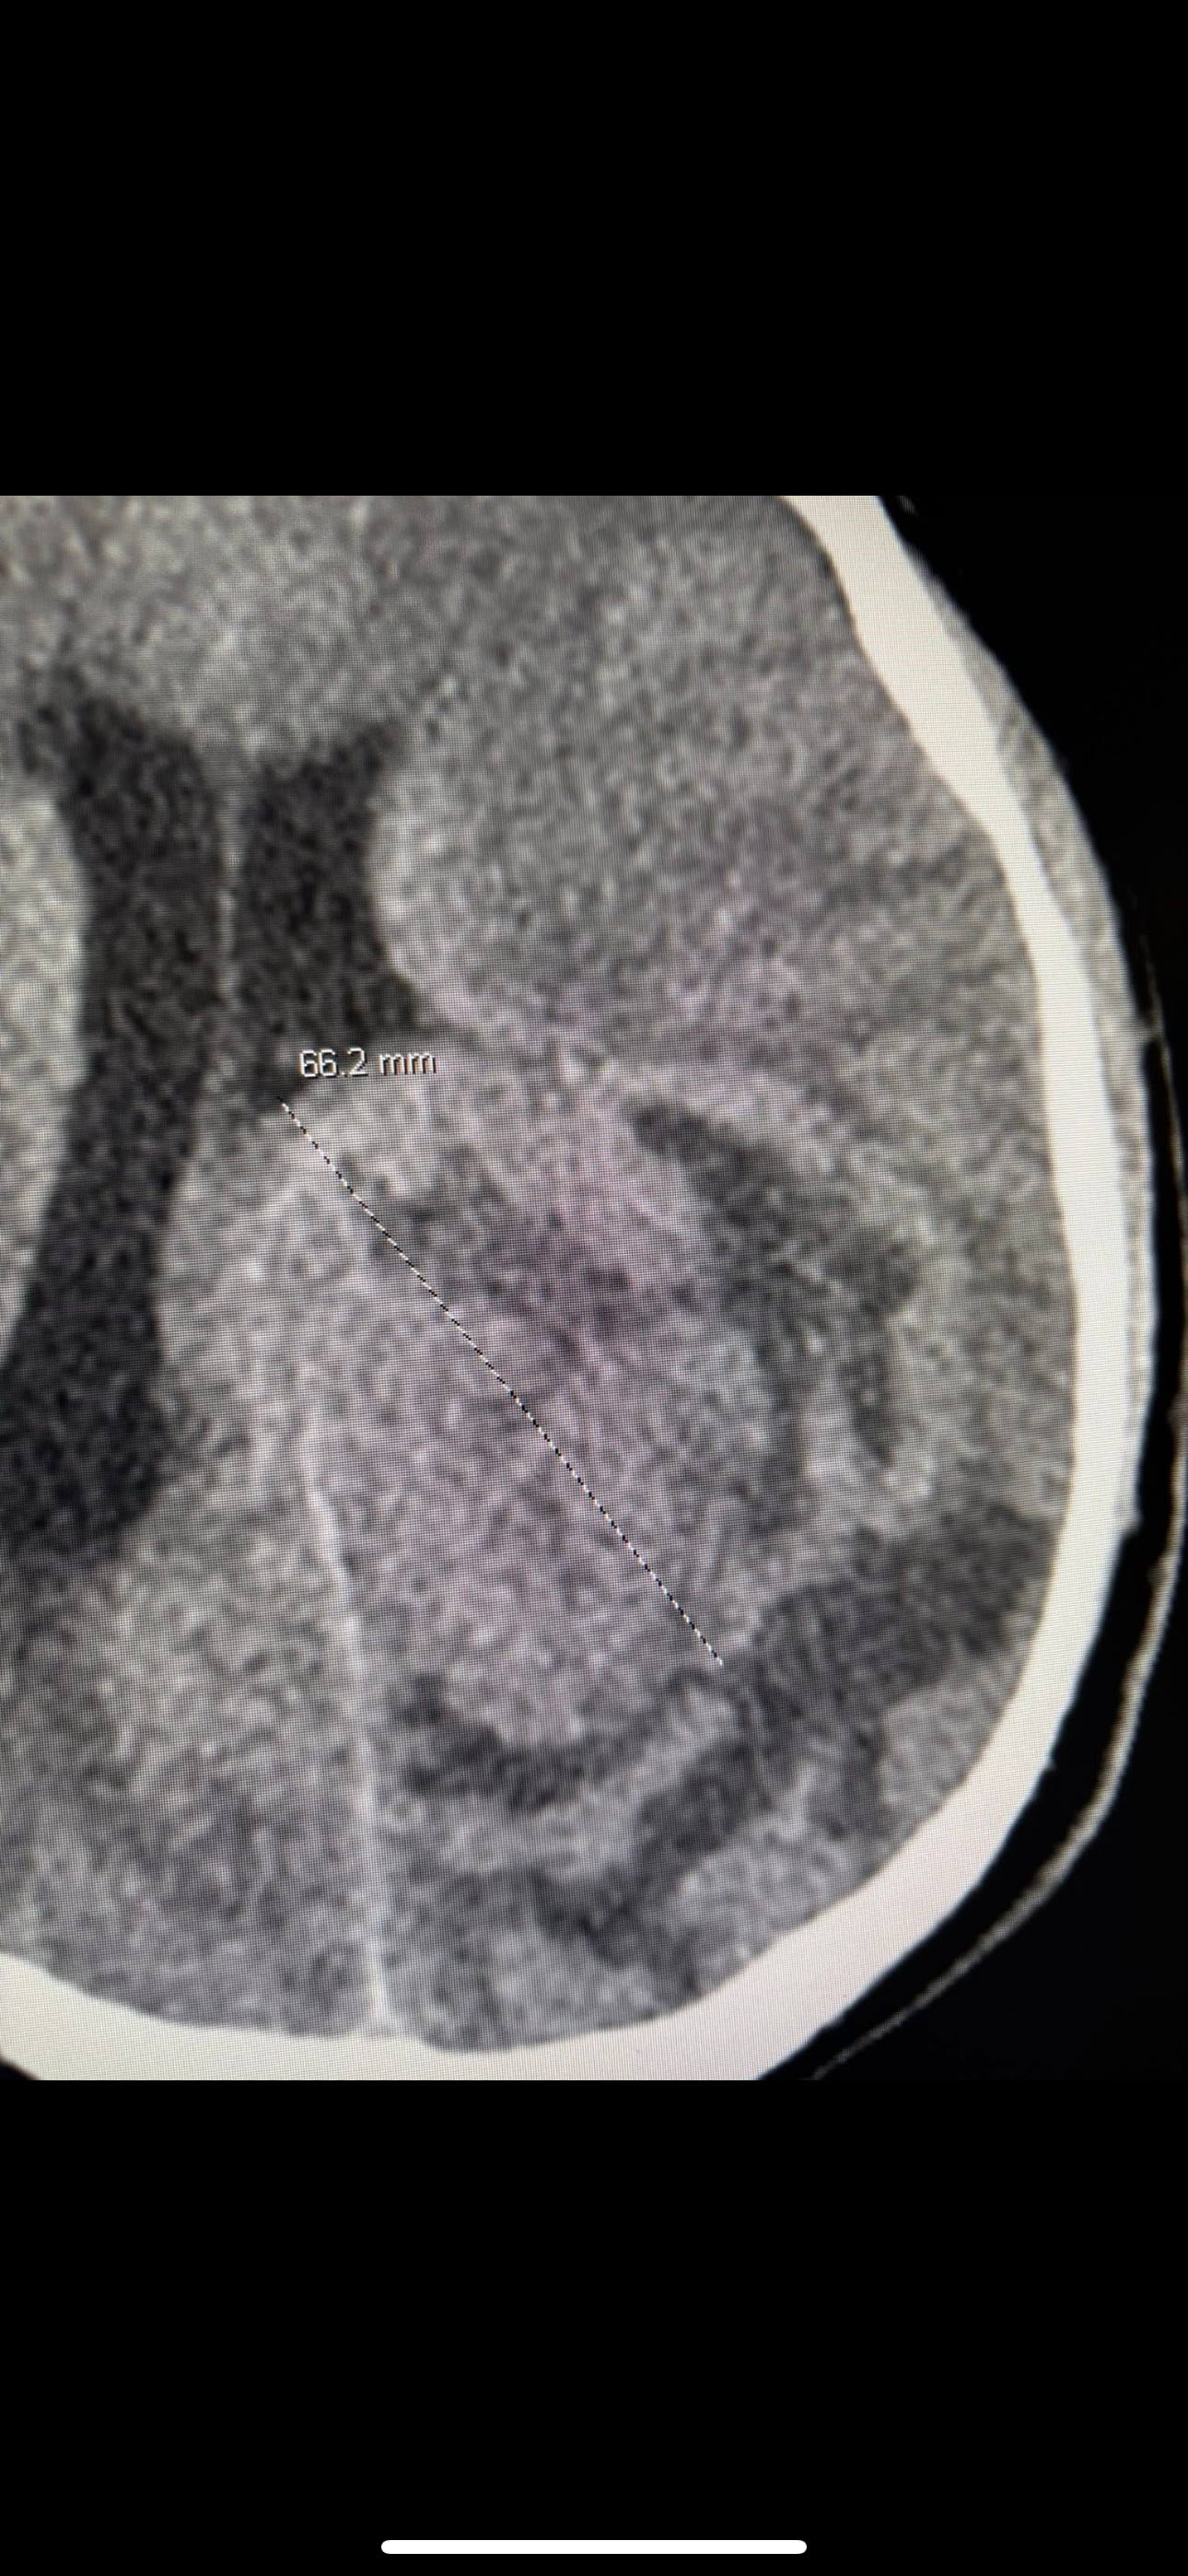

Jared did well today. They were able to get him off the vent. He was eating cheeseburgers and joking around. Unfortunately they only were able to get about 25% of the tumor. They are saying it’s something they’ve never seen before. They said what they didn’t realize during his surgery was as they were “scooping” the tumor it was collapsing in on itself. So they weren’t able to get nearly as much as they thought they did. The mri look just about the same as before the surgery. So now on to plan B. He will remain in the neuroscience ICU. They are giving his brain a few days to heal. Then they want to do an angiogram of the blood vessels in his brain so they can identify the main vessels feeding the tumor. As well as the vessels feeding his brain. Once that is known we still have to wait for pathology report as the first was inconclusive and had to be sent for further testing. Whatever this is, is rare and unknown. Once we get the answers to those two then they will all come together with a plan to go back in and remove, god willing, the remainder of the tumor. This could be in a week. Maybe more maybe a couple days less. He is doing well though. He has issues with his vision and function of his left foot/leg. So for all his friends out there. We are trying to help him as much as we can get through his Snapchat’s and texts. It’s hard for him to read and text back. Please continue the prayers, answers, for complete healing and a prayer for patience for all of us but especially Jared. Who said to me “just tell them to get it out now so I can get back to my life” He is not one to lay around in bed and he was getting anxious about that. So please pray and encourage him to rest and have patience throughout this journey. He is now sound asleep and has had little pain. Thank you everyone!!!! You have no idea how much it means to all of us.

Prayers for J-Rod as we prepare for his second brain surgery tomorrow. We have a couple answers, he has Ependymoma which is a rare CNS tumor that usually occur in younger children. But can occur in teens and young adults as well. We are not sure how long he’s had this but they do feel it’s been pretty slow growing. Imaging has shown that it has not spread. This type can spread through the spine but unlikely to go beyond that. But as far as Jared’s it is localized to the original tumor in his brain. Although massive in size. We thank the good Lord, our Heavenly Father, for that. We don’t have staging yet as that’s an additional and timely part of the pathology and likely won’t have that until next week due to the holiday weekend. Hopes are that he will get the first slot in the AM for surgery. But that’s also dependent on the pediatric neurosurgeon that took over his case. As he has been away on vacation. They want to make absolutely sure he is completely up to date and has a good surgical plan in place. If he needs additional time tomorrow, then so be it and his surgery will be a little later or tomorrow night. PT did get him up using the walker and into the chair. Still lots of struggles with the left side but they were happy with how well he did. It’s a good possibility they will get him in a wheelchair and outside this evening to see the fireworks to local golf course sets off as he can’t see them from his window. That is a process due to his drain. But they are pretty sure we can get that done. Please all continue to keep him in your thoughts and prayers. As always. I thank everyone for the generosity, as of right now there are no medical expenses but we have our expenses to stay here with him, food, accommodations, gas, daily living needs as well as lots of snacks for Jared. Funding also goes to travel back home to take care of things and give his youngest sibling Riley a bit of a break as well as trying to pay bills as I have had a total loss of income right now to be with him and under FMLA. So I thank you all for allowing me to be able to be with my son at all times during this. We pray that after surgery the treatments will be minimal and we are able to get him back home sooner rather than later. There will most likely be at least some radiation therapy depending on if they are able to resect the whole tumor and what the grading/staging is. He will also need physical and occupational therapy, to what extent, we don’t know right now. Again thank you all and I will keep you updated as much as I can after surgery. Let’s get this young man back to the crazy J-Rod that loved to test his mom’s anxiety with his antics.

A little more in depth update from yesterday’s…. Pathology showed a rare tumor called an ependymoma. Only about 200 diagnosed a year. These are usually benign tumors and can be slow or fast growing. They do feel his has been on the slower growing side just based off symptoms. Benign vs cancerous depends on the stage/grade. The highest stage is considered cancerous as it can spread outside the central nervous system and is very aggressive. There is no evidence of that. We are hoping to get that final staging back this week from the lab. Delays due to the holiday weekend. His new surgeon is incredible and has worked with these tumors before. He made us aware of all the mistakes made by the Cedar Crest surgeon. The left side partial paralysis/weakness is due to them going through right side healthy brain to get to the left side tumor and the “bruising, dried blood” on that side has what led to this. He does feel that will resolve with extensive rehab and healing. Last night while helping wash his feet we unintentionally found out he is once again ticklish on that left foot. Which had us all cracking up and gave some relief that feeling is coming back.

So for this tumor. The biggest hurdle is complete resection of it as these tumors do recur and he will be monitored his entire life for them. The hard part is there is a lot of it right by the optic nerve and the nerves that control the RIGHT side of his body. The surgeon does feel that with removal he will experience some of this but is hopeful with in patient rehab his brain and the nerves will bring most or all function back. That’s not something we can predict. Surgery is scheduled for first thing Monday (tomorrow) morning. After surgery, once he is stable they will run another mri to make sure they got it all, as sometimes the margins may get a little “fuzzy” but typically the margins are fairly clear. IF they see anything on the post op MRI they will return to the OR on Tuesday to remove any remaining cells. IF they can safely do so without further complications. If not. Radiation may be needed but radiation is not always helpful with this type of tumor and there is no clinical evidence that supports chemotherapy is helpful. So let’s all prayer for a safe and complete resection!!!

For those that may not follow my facebook posts, I apologize for delayed updates. Jared had his second brain surgery yesterday. Everything went extremely well with no complications. He had a rough night last night from post op pain. This was the first time since that first night we got this diagnosis that he has been in pain and for that we are thankful. For today Jared had less pain today which was great. Still a little more pain this evening but is resting comfortably now after another pain reliever/muscle relaxer cocktail. He got his post op MRI and no visible signs of any remaining tumor!!! Praise God!! We still have a long wait for complete pathology to determine if they will do radiation for any microscopic cells that may linger that imaging can’t pick up. He did get up and in the chair for a bit today. Still struggling with that left foot, so he finally got the brace to help with that when walking. They had originally planned on blocking his “brain drain” or “charging part” (as he calls it) tomorrow for 24 hours and then a CT on Thursday to see how he is doing. But he’s had a slight fever of 100.9 and elevated white blood cell count. So I am not sure at this time if that’s still the plan. They aren’t too concerned but they are being proactive and started him on 2 IV antibiotics while we wait for cultures of the CSF, blood, urine, and nasal swab to come back. Will talk more in the AM to his surgeon to see if that’s still safe to do. If all is safe and clear he may possibly be able to get out of PICU Thursday or Friday and moved upstairs. Please continue to prayer for Jared that this fever is a simple post op fever and not an infection. As well as continued prayers for best possible outcome with pathology and that he will start to regain sensation in the left foot. He still has a long road ahead of him but he is a fighter. Pictures are pre op and post op MRI images.